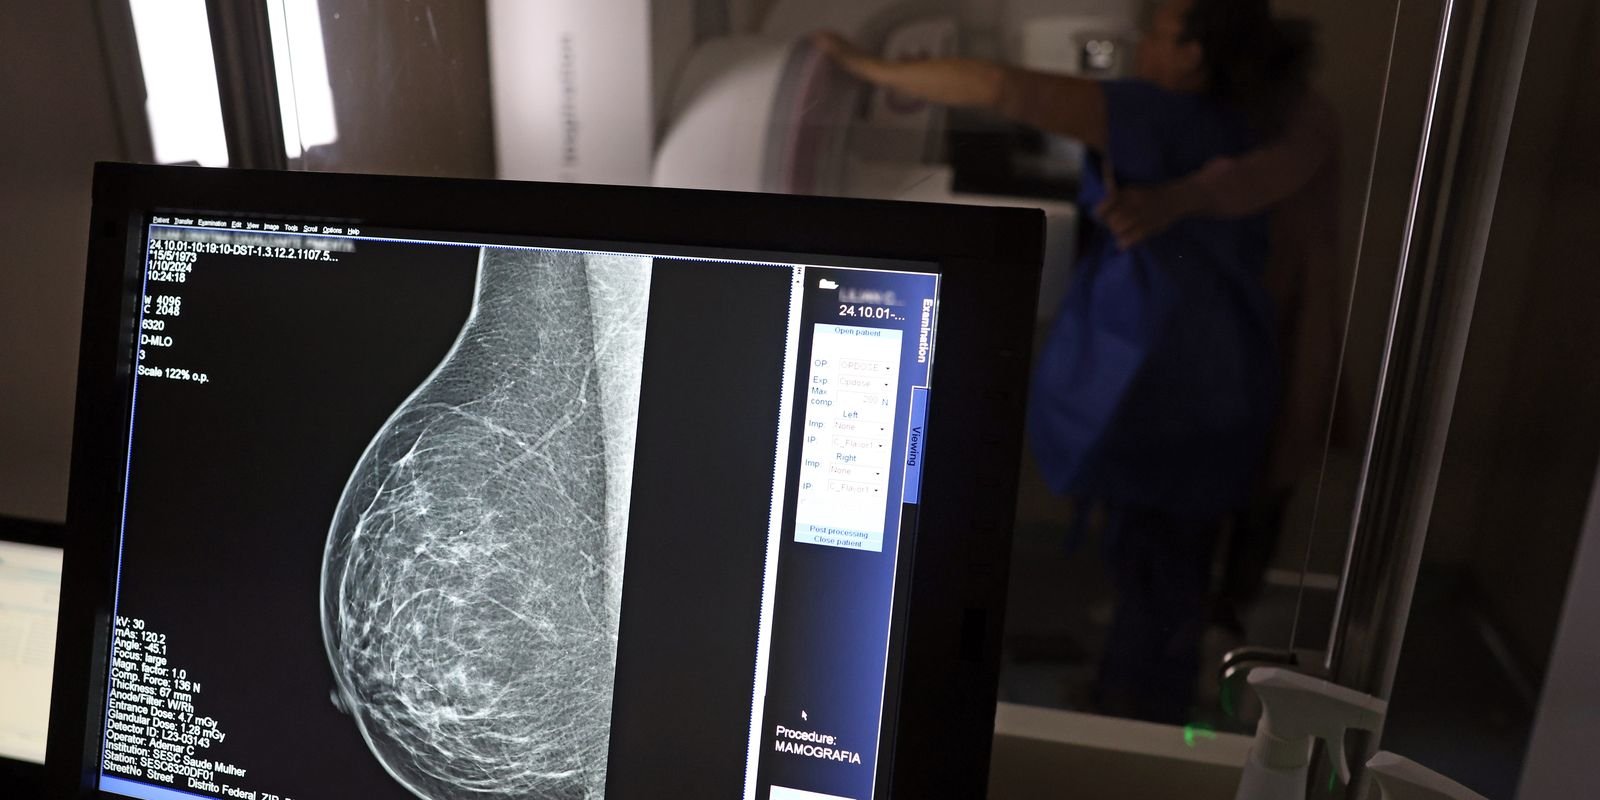

Câncer de mama: uma em cada três pacientes tem menos de 50 anos

Dados do Painel Oncologia Brasil, analisados pelo Colégio Brasileiro de Radiologia e Diagnóstico por Imagem (CBR), indicam que mais de 108 mil mulheres com menos de 50 anos foram diagnosticadas com câncer de mama no Brasil no período entre 2018 e 2023 – uma média de uma em três mulheres diagnosticadas com a doença.

Para a entidade, os números reforçam a importância de ampliar o rastreamento do câncer de mama por meio da realização de mamografia em mulheres abaixo dos 50 anos e acima dos 70 anos, faixas etárias que não estão incluídas na recomendação padrão de exames preventivos no âmbito do Sistema Único de Saúde (SUS).